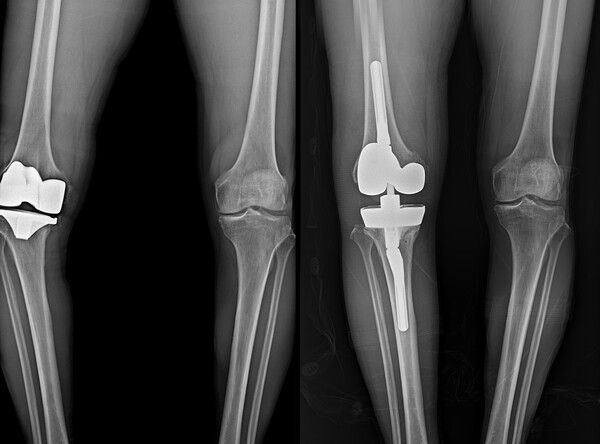

무릎 인공관절 재수술 전(좌), 후(우) 무릎 인공관절 재수술 전(좌), 후(우)

재치환술은 기존에 삽입된 인공관절을 제거하고 새로운 인공관절로 교체하는 수술이다. 단순히 인공관절을 다시 넣는 과정이 아니라 손상된 뼈와 주변 연부조직 상태를 면밀히 평가하고 환자별 조건에 맞는 수술 전략을 세워야 하는 고난도 수술이다. 주로 인공관절의 마모, 느슨해짐, 감염, 골절, 관절 불안정성 등이 발생했을 때 재치환술이 필요하다.